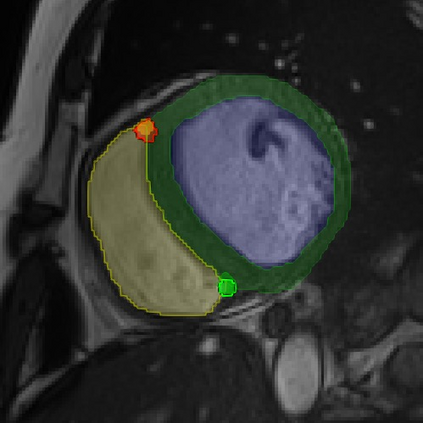

Cardiac Magnetic Resonance (CMR) images are widely used for cardiac diagnosis and ventricular assessment. Extracting specific landmarks like the right ventricular insertion points is of importance for spatial alignment and 3D modeling. The automatic detection of such landmarks has been tackled by multiple groups using Deep Learning, but relatively little attention has been paid to the failure cases of evaluation metrics in this field. In this work, we extended the public ACDC dataset with additional labels of the right ventricular insertion points and compare different variants of a heatmap-based landmark detection pipeline. In this comparison, we demonstrate very likely pitfalls of apparently simple detection and localisation metrics which highlights the importance of a clear detection strategy and the definition of an upper limit for localisation-based metrics. Our preliminary results indicate that a combination of different metrics is necessary, as they yield different winners for method comparison. Additionally, they highlight the need of a comprehensive metric description and evaluation standardisation, especially for the error cases where no metrics could be computed or where no lower/upper boundary of a metric exists. Code and labels: https://github.com/Cardio-AI/rvip_landmark_detection